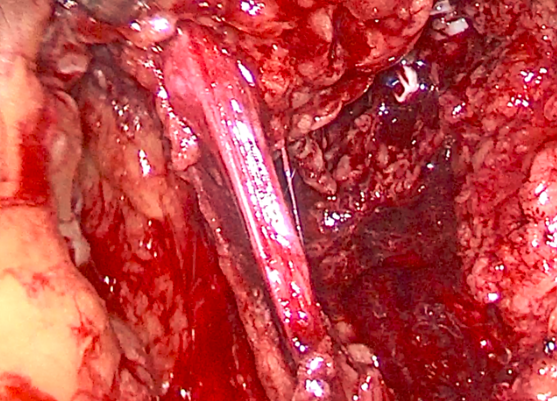

游离肾静脉,发现因长期压迫,肾实质萎缩影响,肾静脉也已萎缩

仔细游离将萎缩的动脉离断,多重夹闭防止出血

完整切除左皮囊肾和输尿管及结石,术中可见皮囊肾如同放了气的气球萎缩一般。